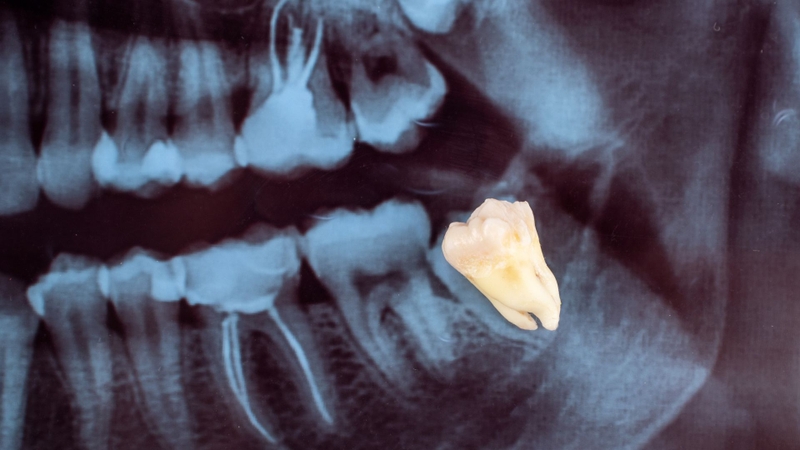

Tuy nhiên, nếu sốt kéo dài hoặc kèm theo sưng to, đau nhiều, bạn cần đi khám. Trong nhiều trường hợp, bác sĩ có thể làm sạch vùng lợi trùm, kê thuốc hoặc chỉ định nhổ răng khôn nếu cần thiết.